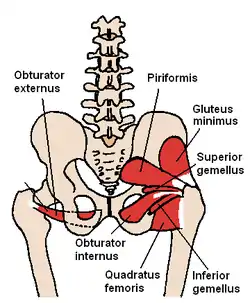

The gluteus minimus and nearby small gluteal muscles (posterior view) | |

Between the gluteus medius and gluteus minimus are the deep branches of the superior gluteal vessels and the superior gluteal nerve.

The muscle may be divided into an anterior and a posterior part, or it may send slips to the piriformis, the superior gemellus or the outer part of the origin of the vastus lateralis.

Position of gluteus minimus muscle (shown in red). Hip bone is shown in semi-transparent. Structures surrounding right hip-joint. (Gluteus minimus visible at center left.)